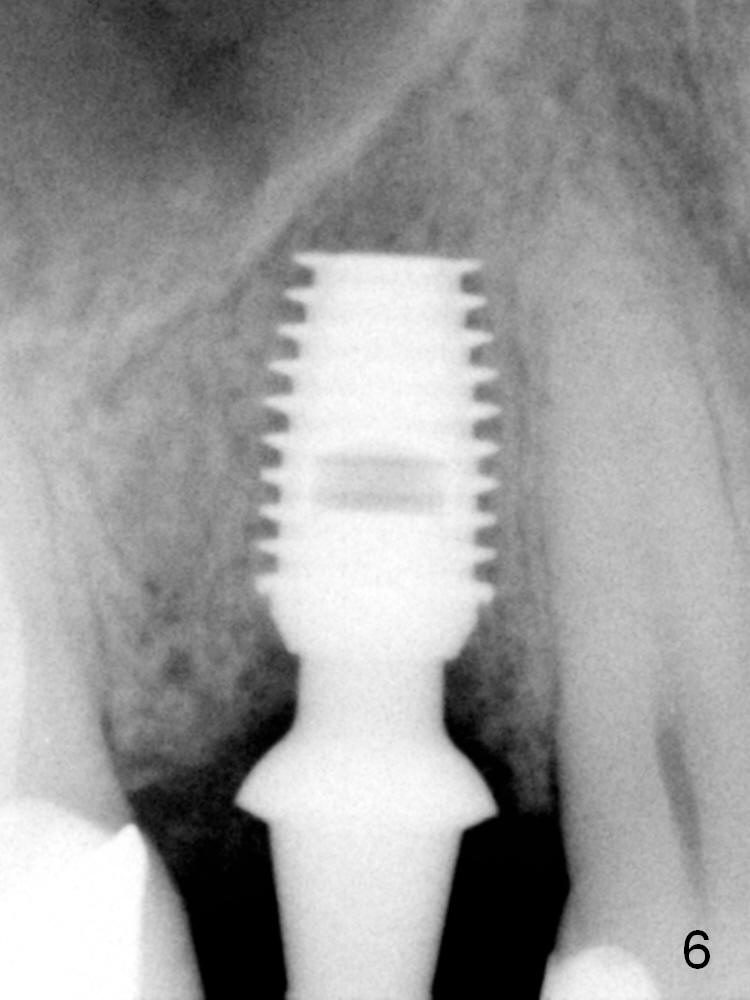

ZC is a 36-year-old man without significant medical history. His chief complaint is "I have Pain sometimes". His oral hygiene is poor (Fig.1). The tooth #3 has large MO caries with periapical radiolucency (*). The tooth #4 is non-salvageable (Fig.1,2). Four months after scaling & root planing, RCT and crown for #3 and extraction of #4 (Fig.3), a 5x8 mm Bicon implant is placed at the site of #4 (Fig.4). Peri-implant space is obliterated 5 months postop (Fig.5). The 2nd surgery is performed to uncover the implant and to place a temporary abutment. Two weeks later, a 5.0x.3.0 mm 0 degree Stealth Abutment 3.0 mm Post is placed (Fig.6). The most recent recall PA shows no bone loss for 5 years 3 months post cementation (Fig.7).